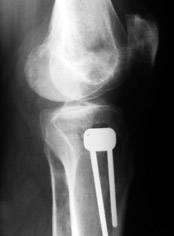

Уважаемые коллеги, много работ посвящено коррекции деформаций конечностей (варусной, вальгусной, торсионной), НЕ ВАЖЕН способ фиксации, важен подход – правильная биомеханическая коррекция, что достигается правильным определением уровня деформации (бедро, голень) и соответственно, правильным определением уровня коррекции.

Аппаратная коррекция очень грамотно изложена в диссертации Белокрылова Николая Михайловича «Хирургическая тактика лечения деформирующего гонартроза» Пермь 1998г. В моей работе описаны методы коррекции с накостным остеосинтезом. «Корригирующие операции в лечении гонартроза» Москва 2003г.